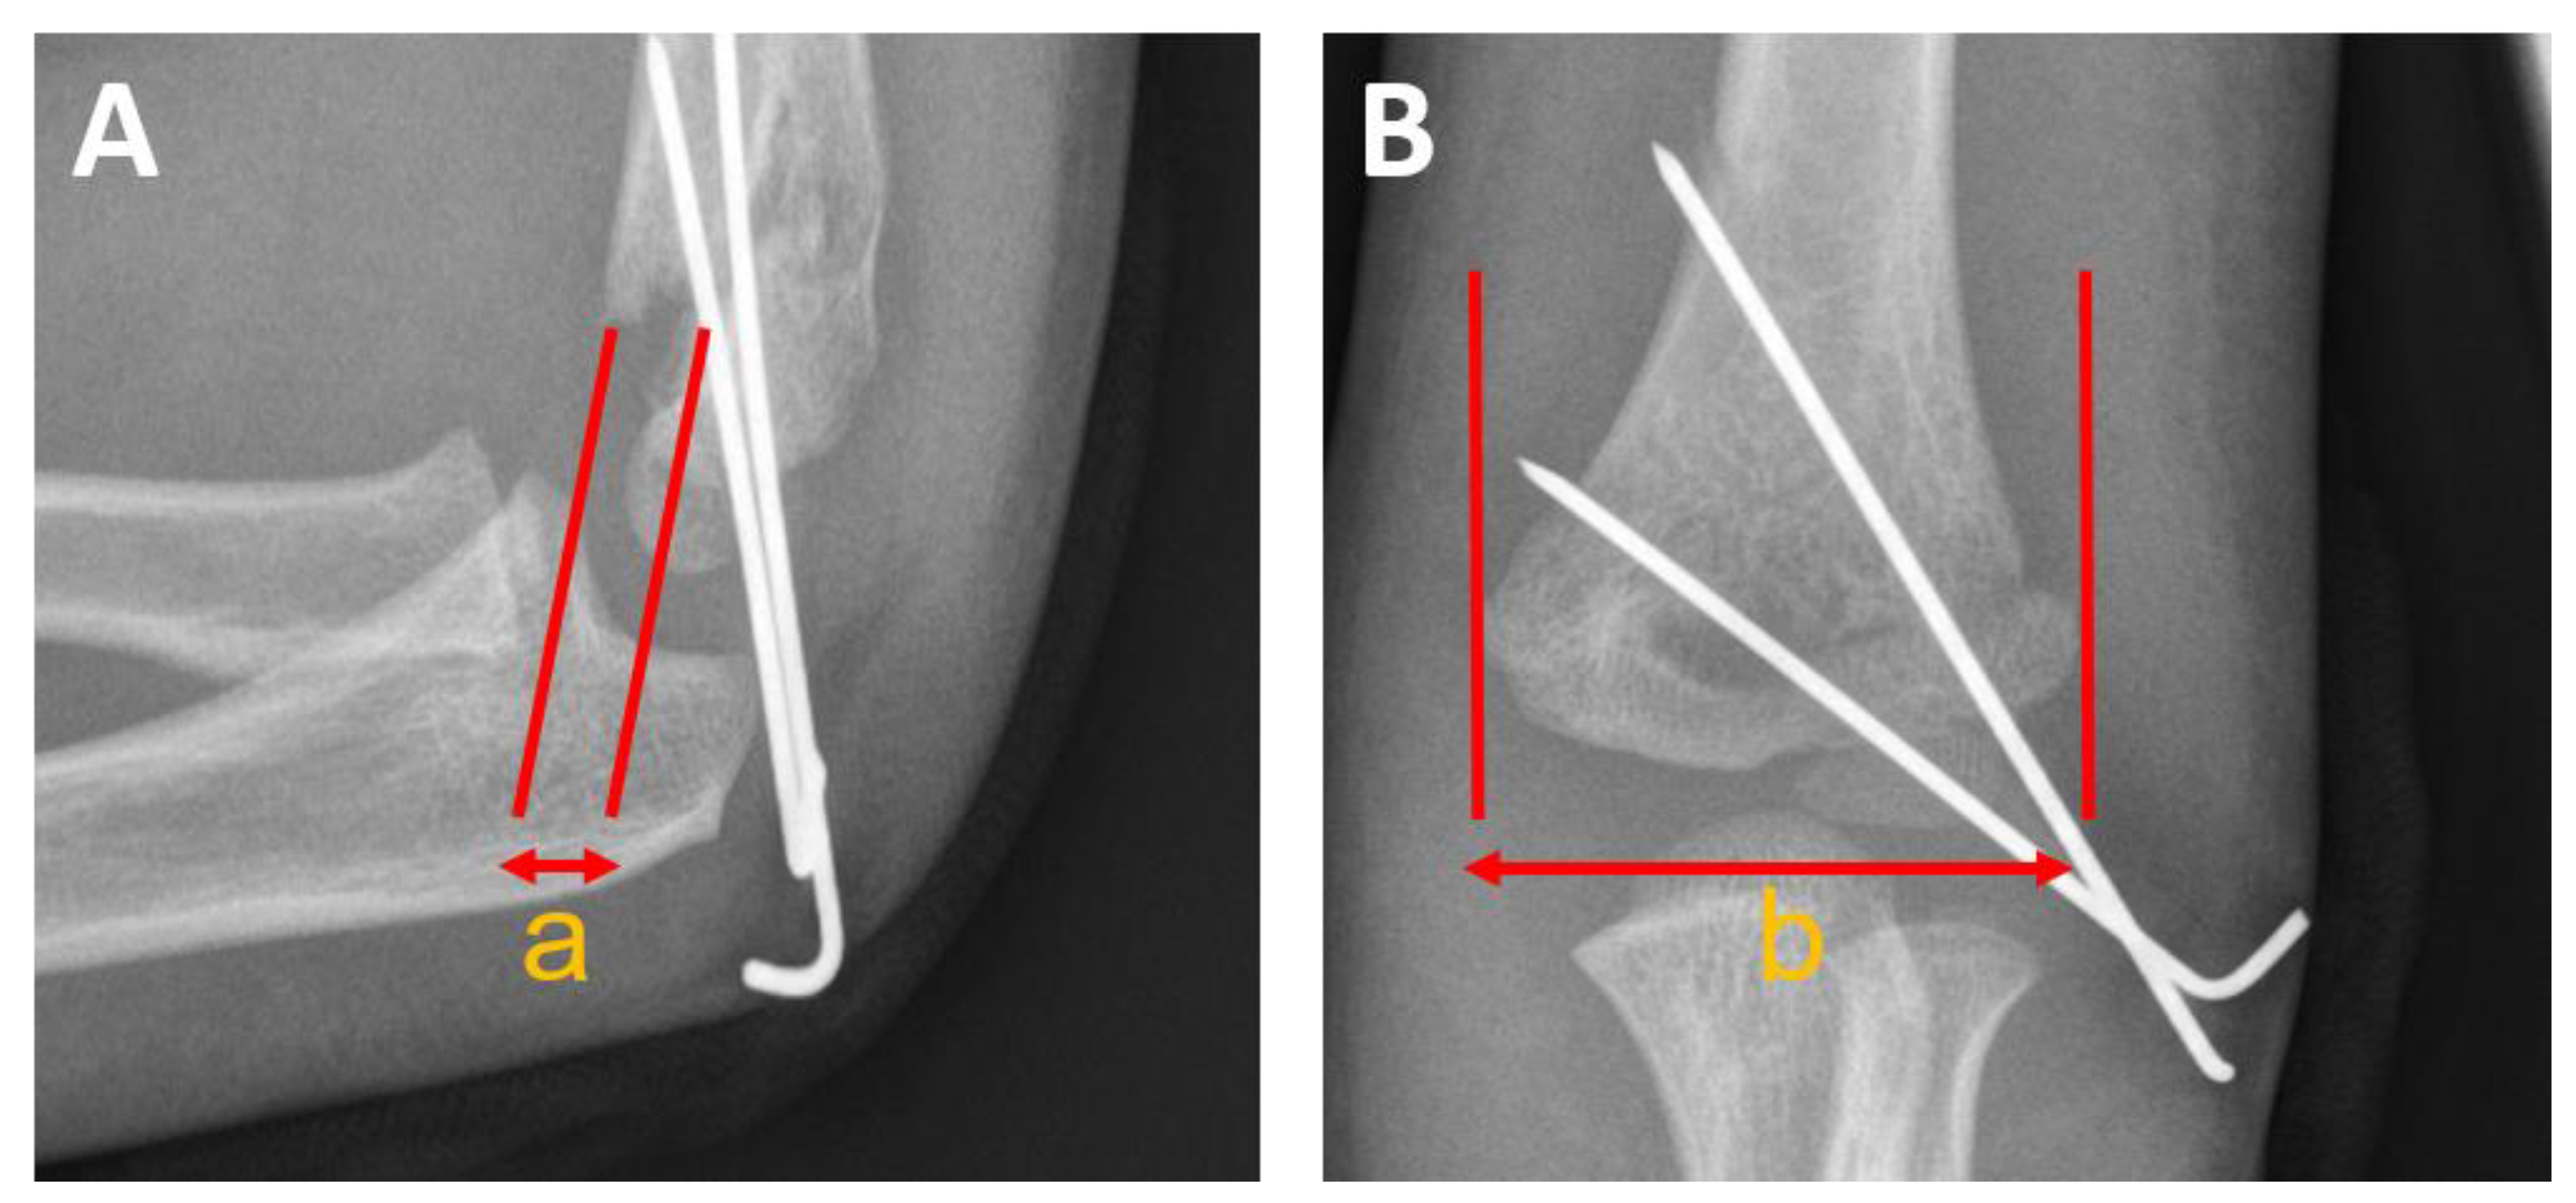

2.2. Surgical Technique

2.2.2. Retention by Antegrade Nailing (AN)

2.2.3. Retention by Percutaneous crossed Pinning (PCP)

3.5. Postoperative Malrotation

- Greve, F.; Müller, M.; Wurm, M.; Biberthaler, P.; Singer, G.; Till, H.; Wegmann, H. Standalone Axial Malrotation after Pediatric Supracondylar Fracture Does Not Seem to Be an Indication for Immediate Postoperative Revision Surgery. Children 2022, 9, 1013. [Google Scholar] [CrossRef]